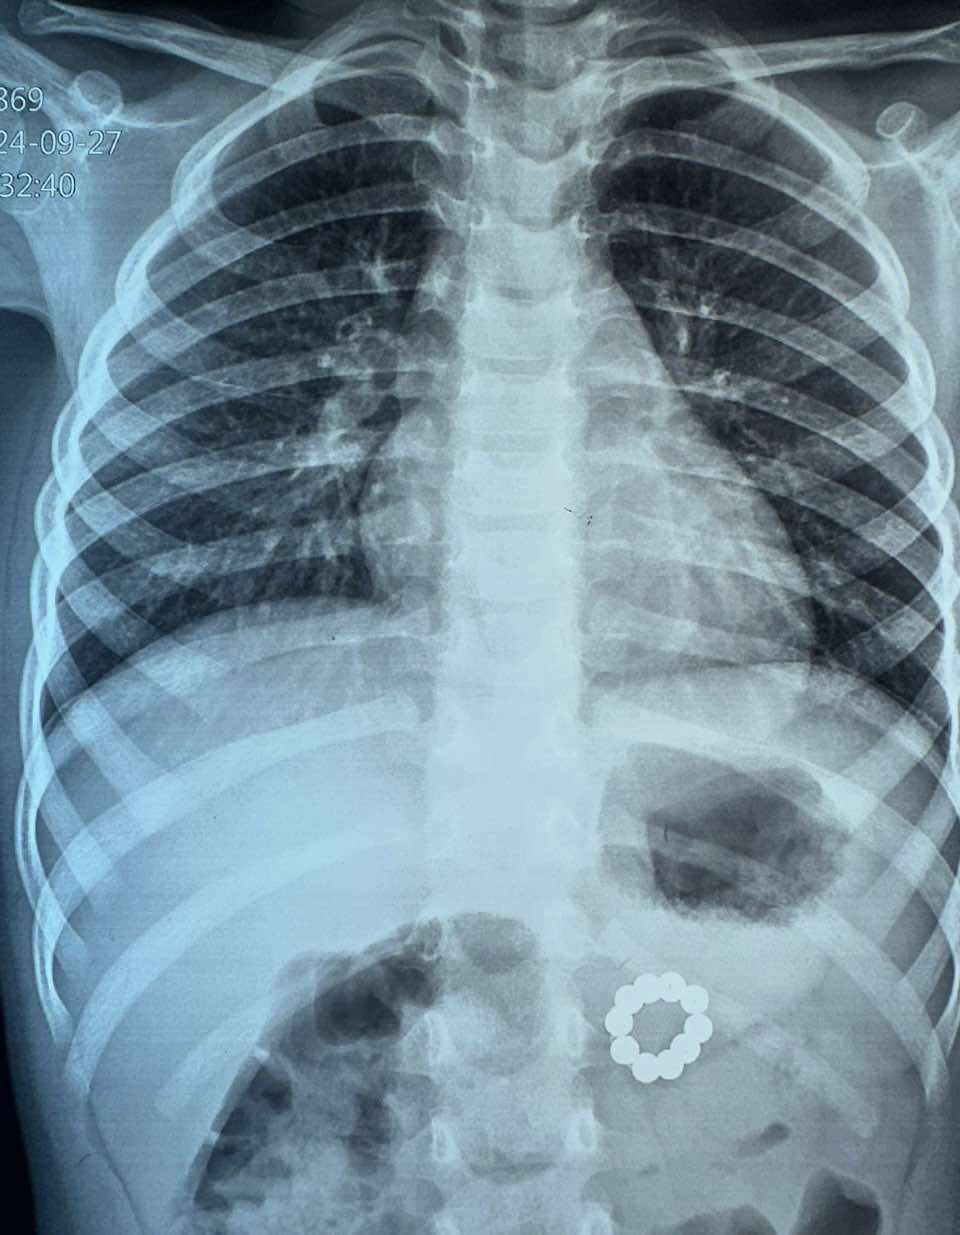

В Івано-Франківській обласній дитячій лікарні прооперували 3-річну дівчинку. З її шлунково-кишкового тракту витягнули 21 неодимовий магніт.

З його слів, у лікарню звернулася мати з дитиною. Її донька скаржилася на кашель та біль в животі. При обстеженні у шлунково-кишковому тракті дитини медики виявили неодимові магніти.

Видалення ендоскопічно не було можливе. Тому провели оперативне втручання, у результаті якого видалили 10 магнітів з товщі задньої стінки шлунку і ще 11 — з початкового відділу здухвинної кишки, — написав Тарас Мельник.